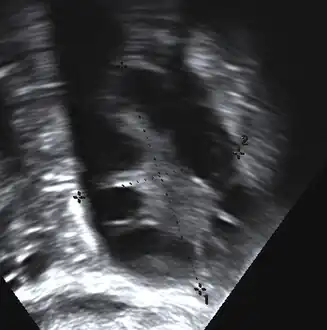

Transvaginal ultrasound scan of polycystic ovary

- Gynecologic ultrasonography, specifically looking for small ovarian follicles. These are believed to be the result of disturbed ovarian function with failed ovulation, reflected by the infrequent or absent menstruation that is typical of the condition. In a normal menstrual cycle, one egg is released from a dominant follicle – in essence, a cyst that bursts to release the egg. After ovulation, the follicle remnant is transformed into a progesterone-producing corpus luteum, which shrinks and disappears after approximately 12–14 days. In PCOS, there is a so-called "follicular arrest"; i.e., several follicles develop to a size of 5–7 mm, but not further. No single follicle reaches the preovulatory size (16 mm or more). According to the Rotterdam criteria, which are widely used for diagnosis of PCOS,[10] 12 or more small follicles should be seen in a suspect ovary on ultrasound examination.[21] More recent research suggests that there should be at least 25 follicles in an ovary to designate it as having polycystic ovarian morphology (PCOM) in women aged 18–35 years.[95] The follicles may be oriented in the periphery, giving the appearance of a 'string of pearls'.[96] If a high-resolution transvaginal ultrasonography machine is not available, an ovarian volume of at least 10 ml is regarded as an acceptable definition of having polycystic ovarian morphology. rather than follicle count.[95]

Ultrasound findings in PCOS include enlarged ovaries with peripheral follicles in a "string of pearls" configuration.